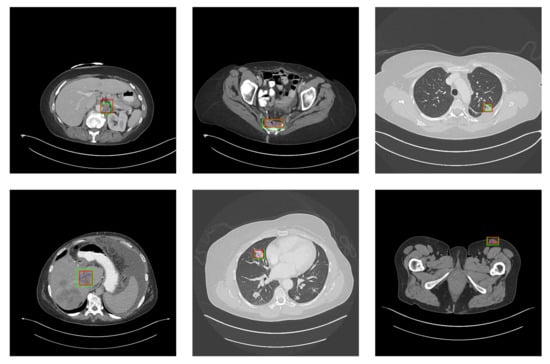

5.2. Detection Results

For further comparison, we extracted six images from the CT image series of DeepLesion. These images were taken from different sites of lesions and different areas of lesions, showing the detection results of the comparison model as comprehensively as possible. Figure 10, Figure 11, Figure 12, Figure 13, Figure 14, Figure 15, Figure 16, Figure 17, Figure 18 and Figure 19 show the detection results. All green boxes represent ground truth; red boxes denote predicted bounding boxes. It can be seen that Faster-RCNN performs very poorly on small lesions and lesions that are not easy to identify, while YOLO v3, YOLO v4, and SSD series perform relatively well. However, the aspect regression of the bounding box at small lesion locations is still not accurate. On the other hand, EfficientDet, Mask-RCNN, and YOLO v5 perform relatively well and detect lesions accurately. This may be related to the attention extraction module in these networks.

Figure 12.

The detection results of YOLO v5 in the DeepLesion dataset. The green box marks the location of the lesion.

Figure 13.

The detection results of Faster-RCNN in the DeepLesion dataset. The green box marks the location of the lesion.